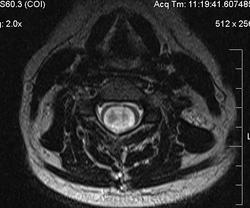

Убедительных данных за патологическое накопление контрастного препарата не выявлено. Кисты с повышенным содержанием белка (?), может быть бывают атеромы в области мягких тканей шеи (гиперинтенсивные по Т1 между мышцами шеи справа)?

Cпасибо большое, как вы думаете, это  кисты в области мягких тканей шеи справа (гиперинтеснивные по Т1 и Т2), или что-то другое?

морфологически- явно кистозные образования. А вот их происхождение - вопрос.